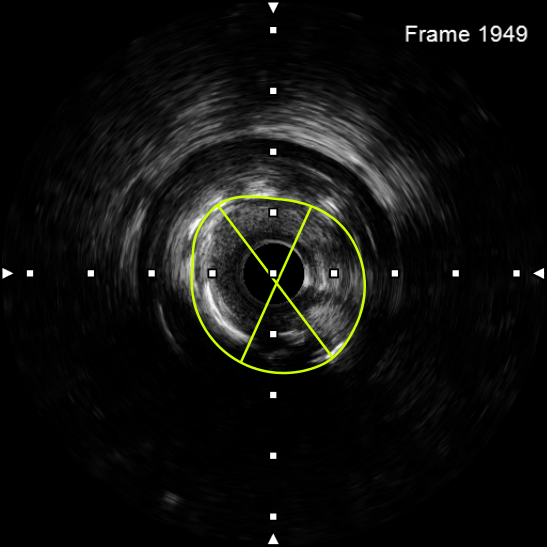

该患者入院后,完善相关检查并再次建议行CABG治疗,但家属仍拒绝,遂考虑再次行PCI手术干预。冠脉造影提示患者冠脉右冠状动脉中段70-95%再狭窄,左主干末端80%狭窄,前降支原支架中远段 80-95%再狭窄,回旋支完全闭塞,急需手术尽快解决冠脉血流灌注问题,否则随时有生命风险,但患者多处支架内/节段内再狭窄,造影提示钙化明显,外院已尝试无法扩张,经手术团队充分讨论后,计划在IABP支持下,先进行右冠状动脉干预,利用IVUS精准评估原支架再狭窄部位情况,采用旋磨或Shockwave冲击波球囊处理无法扩张的病变部位,右冠处理后择期进行左冠状动脉干预。在制定了详尽的手术计划后,手术团队首先对患者的右冠状动脉行IVUS检查,结果提示该患者右冠中段支架局部膨胀不良,局部支架面积6.67mm²,管腔内多处可见钙化小结及270°以上钙化,IVUS钙化积分达3分。由于膨胀不良处原支架后方可见钙化斑块,常规旋磨效果不佳,对于此类钙化病变,IVL处理是最佳方案。手术团队对近端采取棘突球囊及高压球囊进行扩张,采用Guidezilla辅助下输送3.0mmx12mm Shockwave冲击波球囊于右冠钙化处进行冲击波钙化斑块碎裂术,通过IVUS证实支架内的新生钙化病变得到松解,原膨胀不良部位支架面积达到7.76mm²,后经过高压球囊充分预处理,顺利完成右冠支架植入,术后复查右冠原膨胀不良部位支架面积9.17mm²。

图4 3.0 Shockwave处理后可见钙化断裂 高压球囊验证膨胀良好